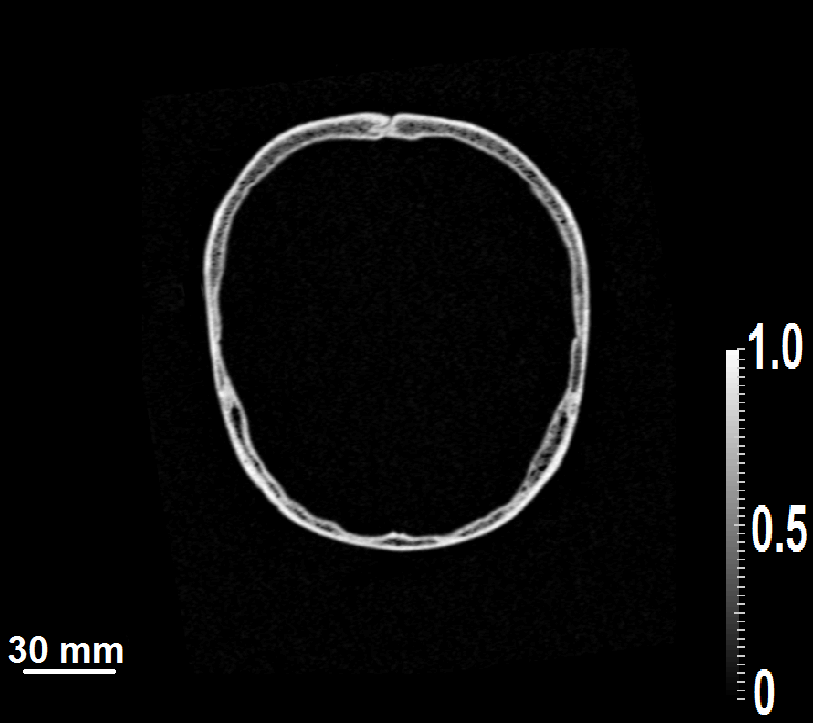

Figure 3: (a) The 3D scanning geometry used for the computer-simulation studies. (b) A 2D slice of X-ray CT image of the skull and (c) the corresponding mask generated by the segmentation algorithm.

The linear isotropic, elastic medium used in the simulation studies was generated from 3D X-ray CT images of a human skull. The intact human skull was purchased from Skull Unlimited International Inc. (Oklahoma City, OK) and was donated by an 83-year-old Caucasian male. The CT images were employed to infer the thickness and contour of the skull.

For the simulation studies involving superscript\mathbb{H}^{\dagger}, we assumed the skull to be an acoustically homogeneous elastic linear isotropic medium. While we consider a relatively simple skull model, the proposed approach could also be applied for more complex skull models, such as those that consider the heterogeneity within the skull. In that case, more effort may be required to accurately estimate the acoustic properties of the skull. In order to extract the contour and location of the skull from CT images, a segmentation algorithm was employed. The segmentation algorithm generated a binary mask specifying the location of the skull within the 3D volume. A 2D slice of the CT image acquired from the human skull and the corresponding mask generated by use of the segmentation algorithm are shown in Fig. 3b and Fig. 3c, respectively. The medium parameters in the 3D grid were assigned such that the skull acoustic parameters (ρ=1850kgm3𝜌1850kgsuperscriptm3\rho=1850\ \frac{\text{kg}}{\text{m}^{3}}, cl=3.0mmμssubscript𝑐𝑙3.0mm𝜇sc_{l}=3.0\ \frac{\text{mm}}{\mu\text{s}}, cs=1.5mmμssubscript𝑐𝑠1.5mm𝜇sc_{s}=1.5\ \frac{\text{mm}}{\mu\text{s}} and α=0.11μs𝛼0.11𝜇s\alpha=0.1\ \frac{1}{\mu\text{s}}) were set at all grid positions where mask was equal to one and the background acoustic parameters (ρ=1000kgm3𝜌1000kgsuperscriptm3\rho=1000\ \frac{\text{kg}}{\text{m}^{3}}, cl=1.5mmμssubscript𝑐𝑙1.5mm𝜇sc_{l}=1.5\ \frac{\text{mm}}{\mu\text{s}}, cs=0.0mmμssubscript𝑐𝑠0.0mm𝜇sc_{s}=0.0\ \frac{\text{mm}}{\mu\text{s}} and α=0.01μs𝛼0.01𝜇s\alpha=0.0\ \frac{1}{\mu\text{s}}) were set at all grid positions where mask was equal to zero. At the material interface between the skull and the background fluid medium, the density and the absorption values were arithmetically averaged to avoid any instability issues with the FDTD wave equation solver.